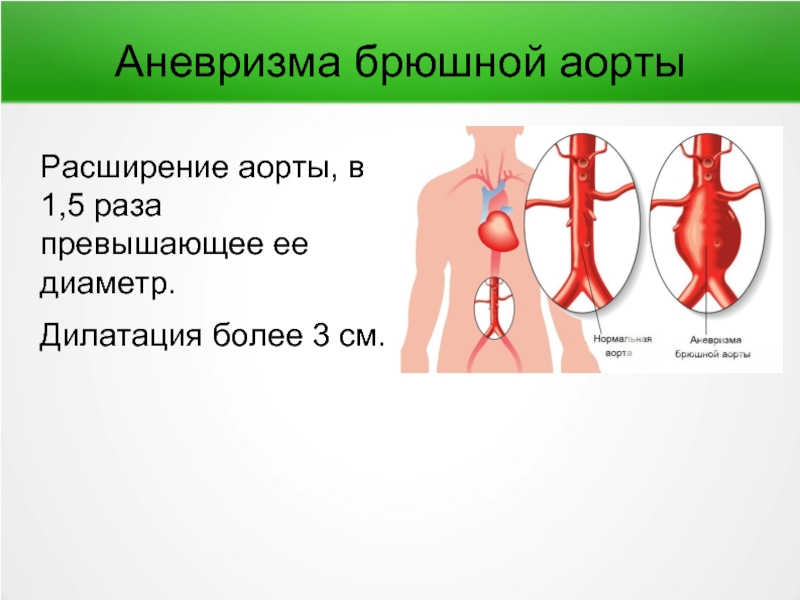

Нормальный диаметр корня аорты: медицинские нормы и отклонения